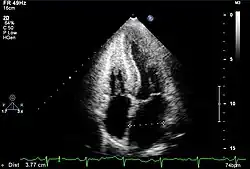

Apparent left ventricular hypertrophy and “snowstorm” appearance of the myocardium are suggestive of an infiltrative cardiomyopathy.